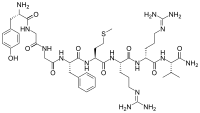

| Opioid peptides | Skeletal molecular images |

| Adrenorphin |  |

| Amidorphin |  |

| Casomorphin | |

| DADLE | |

| DAMGO |  |

| Dermorphin | |

| Endomorphin |  |

| Morphiceptin |  |

| Nociceptin |  |

| Octreotide |  |

| Opiorphin |  |

| TRIMU 5 |  |